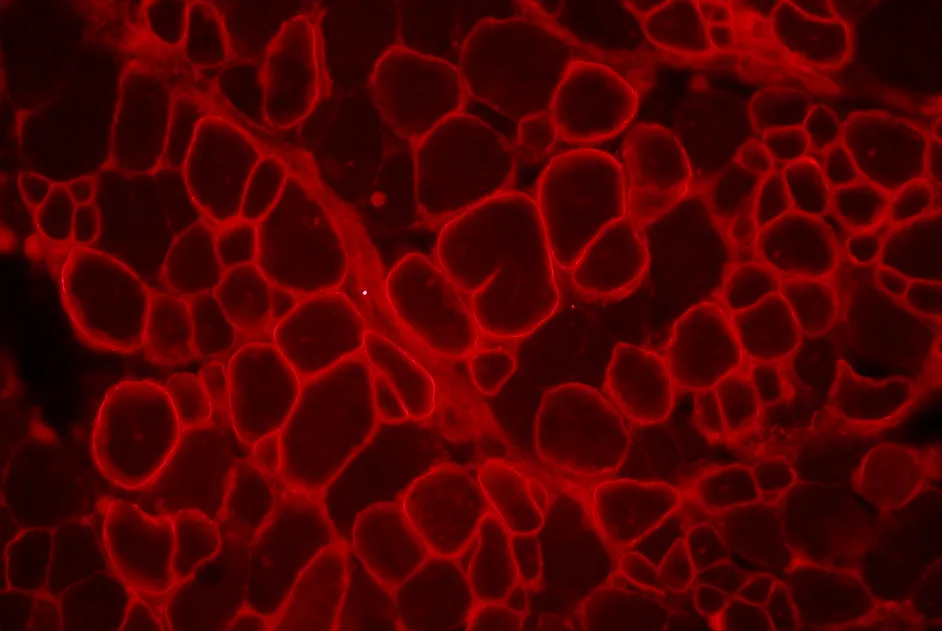

Des anticorps dirigés contre différentes parties de la dystrophine permettent de reconnaitre la dystrophine produites par des fibres révertantes.

Dans la myopathie de Duchenne, il existe des fibres musculaires nommées « révertantes » qui expriment naturellement de la dystrophine, mais celle-ci présente un ou plusieurs régions en moins.

Dans un article publié en décembre 2013, une équipe britannique rapportent la mise au point d'anticorps reconnaissant spécifiquement les différentes régions de la dystrophine. Il existe à présent présent des anticorps anti-dystrophine dirigés contre 25 régions différentes de la dystrophine.

Ces outils représentent un intérêt majeur dans les essais cliniques pour évaluer l’efficacité de la thérapie génique ou cellulaire, car ils permettent de faire la différence entre la dystrophine produite naturellement par les fibres révertantes et la dystrophine normale produite par thérapie génique ou cellulaire.